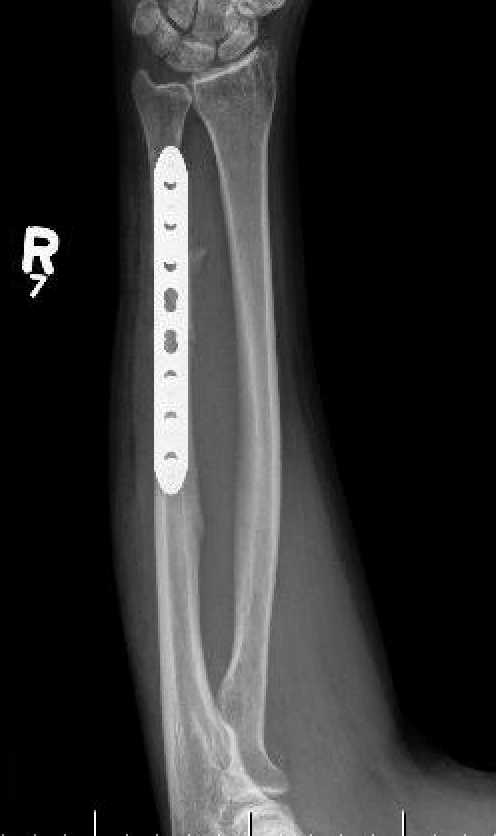

Compression plating

Intra-medullary nail

Ulna Intramedullary WireUlna Plating

Technique

AO foundation ulna plating